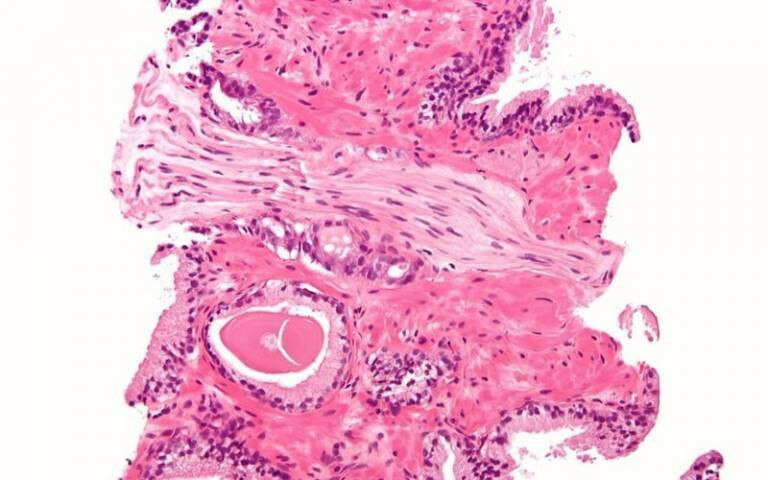

New combination of old drugs improves survival of prostate cancer - Prostatic adenocarcinoma with perineural invasion. Credit:  Nephron  on  Wikimedia Commons  (CC BY-SA 3.0)

New combination of old drugs improves survival of prostate cancer - Prostatic adenocarcinoma with perineural invasion. Credit:  Nephron  on  Wikimedia Commons  (CC BY-SA 3. Adding abiraterone to the standard treatment for locally advanced prostate cancer, where the cancer has a high chance of spreading, could halve the risk of death from the disease, according to the results of a UCL-led trial. The researchers suggest that hormone therapy using abiraterone with prednisolone, could significantly reduce prostate cancer deaths and improve outcomes for thousands of people every year. Using abiraterone for this group of people is now being considered for use in NHS England based on this research. If successful, it could be rolled out to patients immediately. The study, published in the Lancet , is part of the STAMPEDE trial and was led by a team at the UCL Cancer Institute with collaborators at The Institute of Cancer Research, London and funded by Cancer Research UK and the MRC.